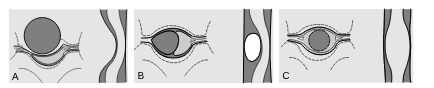

La déformation de la moelle spinale et l’aspect des vertèbres et du sac dural déterminent le type de compression (figure 52.1), ce qui oriente vers la nature de la lésion en cause (tableau 52.1).

Fig. 52.1. Les différents types de compression.

Compression de type extradural (A) : la lésion du corps vertébral refoule la dure-mère. Les espaces sous-arachnoïdiens sont « rétrécis » par la lésion. Compression de type intradural extramédullaire (B) : la lésion est située dans les espaces sous-arachnoïdiens ; elle déplace le cordon médullaire et « élargit » les espaces sous-arachnoïdiens. Compression de type intramédullaire (C) : la lésion est située dans la moelle spinale ; elle élargit celle-ci sur toutes les coupes ; les espaces sous-arachnoïdiens sont « rétrécis ».

Source : CERF, CNEBMN, 2022.